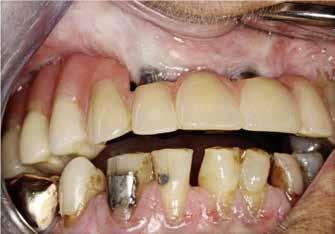

Zygomaimplantater anvendt i særlige patienttilfælde / 574

Vi ser på anvendelsen af zygomaimplantater, som er en mulighed hos patienter, hvor knogleopbygning ikke er en mulighed.